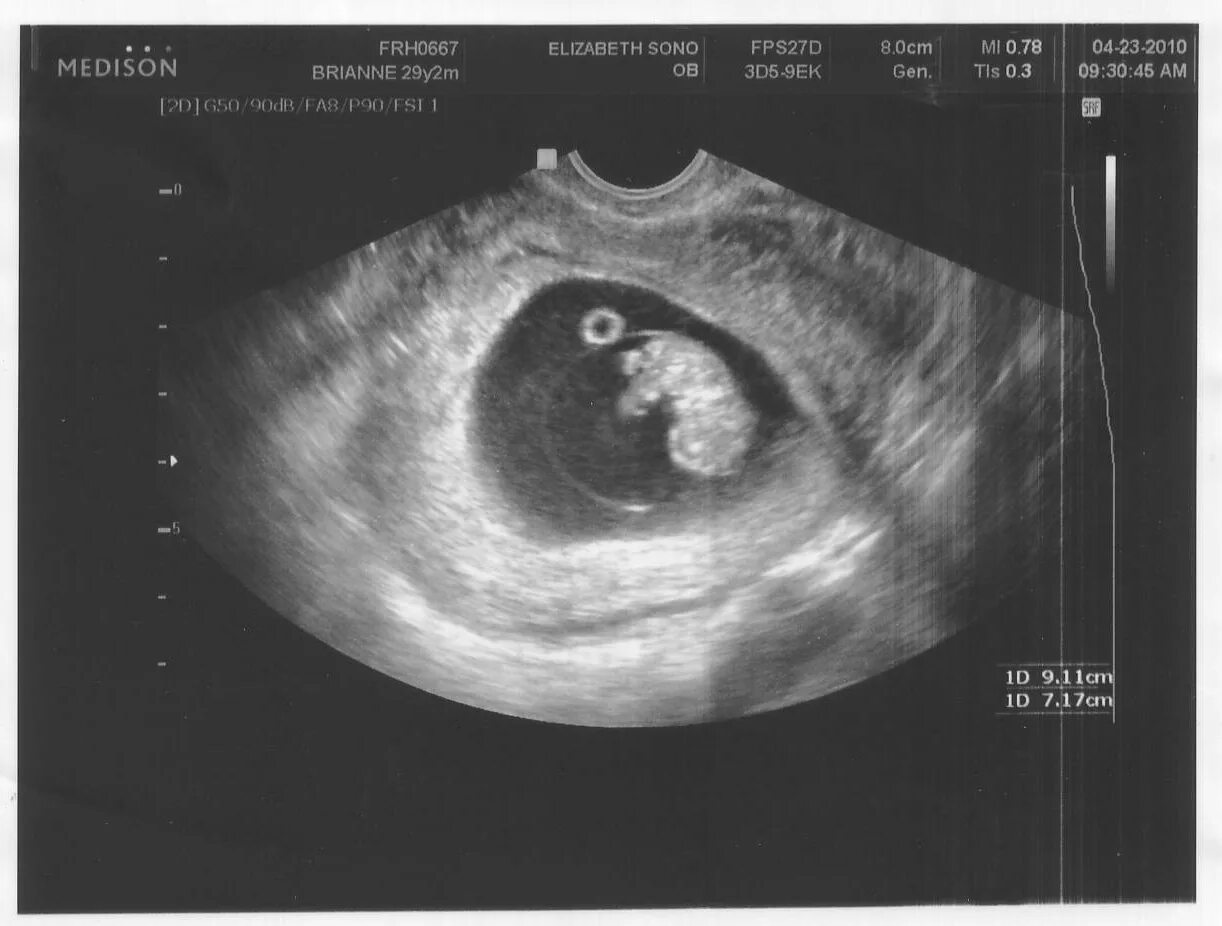

7 недель ощущения